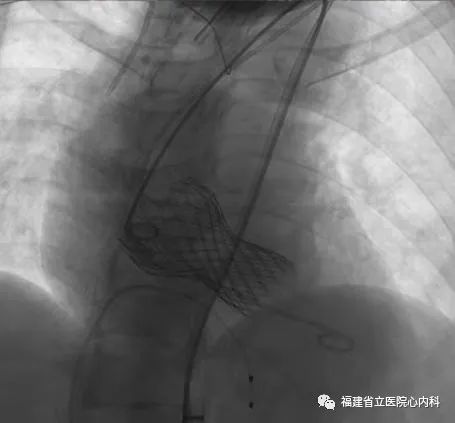

病例4

该病例是三叶瓣,中度钙化,法式窦结构可,但是左冠状动脉开口低,左冠瓣瓣叶冗长,预测掀起的瓣叶可能超过冠脉开口上缘,术者在术前通过CT精准评估冠脉风险,制定详尽的介入治疗策略,术中通过25号球囊预扩进一步确认冠脉情况,最后将29号瓣膜精准植入预期位置,避免冠脉风险,达到预期手术效果。

瓣环

窦部

左冠高度:8.2mm

瓣叶长度:14.9mm

球囊预扩张

植入L29瓣膜